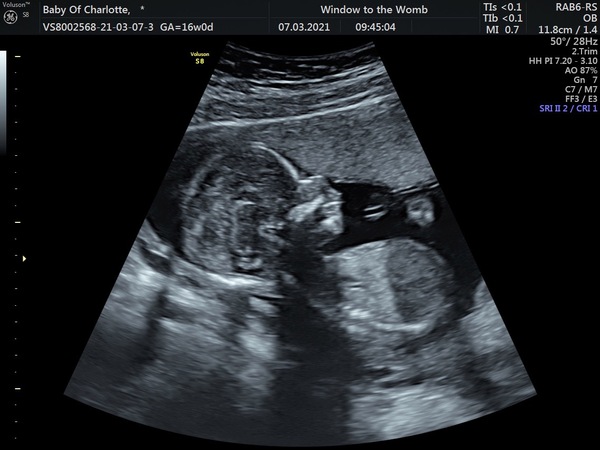

LottSE20 · 07/03/2021 14:07

On a more positive note, I had a 16w scan today and everything was fine (I’d been worrying since that cramping earlier in the week). I also found out we’re having a little boy! Feeling very excited now! DH and have been trying out names ever since.

Here’s the little fella Smile

Lovely scan @LottSE20 and nice that you’re feeling excited too.

How lovely @LottSE20, lovely that you’re excited and starting to think of names.

Lovely scan @LottSE20! 💙

@LottSE20 what a little cutie! Congratulations on finding out it’s a little boy 💙. I just either have a little bloated bump or coz I had a very small pooch when not pregnant - that shows up.

Nice scan @LottSE20!

Lovely scan photo @LottSE20 !

@LottSE20 lovely scan!